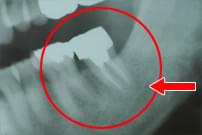

55歳 男性

右下6番の根尖まで進行した歯周病と根尖病巣。

右下6番を抜歯して根のクリーニング、根尖の膿胞を除去して再植。